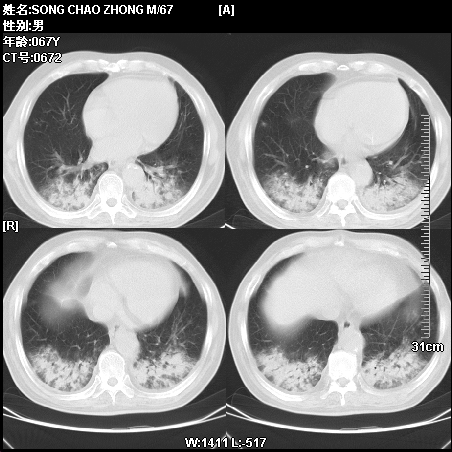

肿瘤科住院病人,都有食管癌史,都有放化疗治疗,两下肺病变是转移灶?还是其他原因造成?请老师指点

病例二 食管癌4个月,咳嗽咳痰,呼吸困难